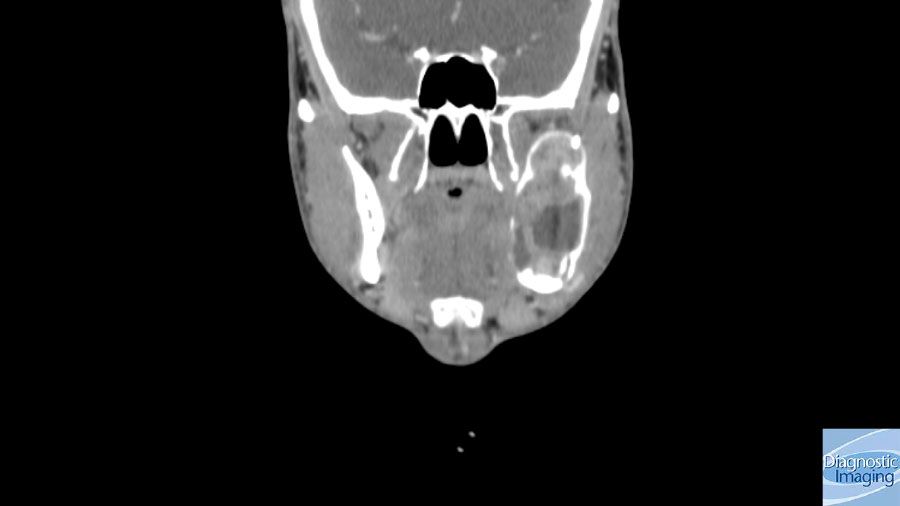

Case History: 57-year-old patient with longstanding history of swelling on left side of face and difficulty opening mouth.

Case History: 57-year-old patient presented with longstanding history of swelling on left side of face and difficulty opening mouth.